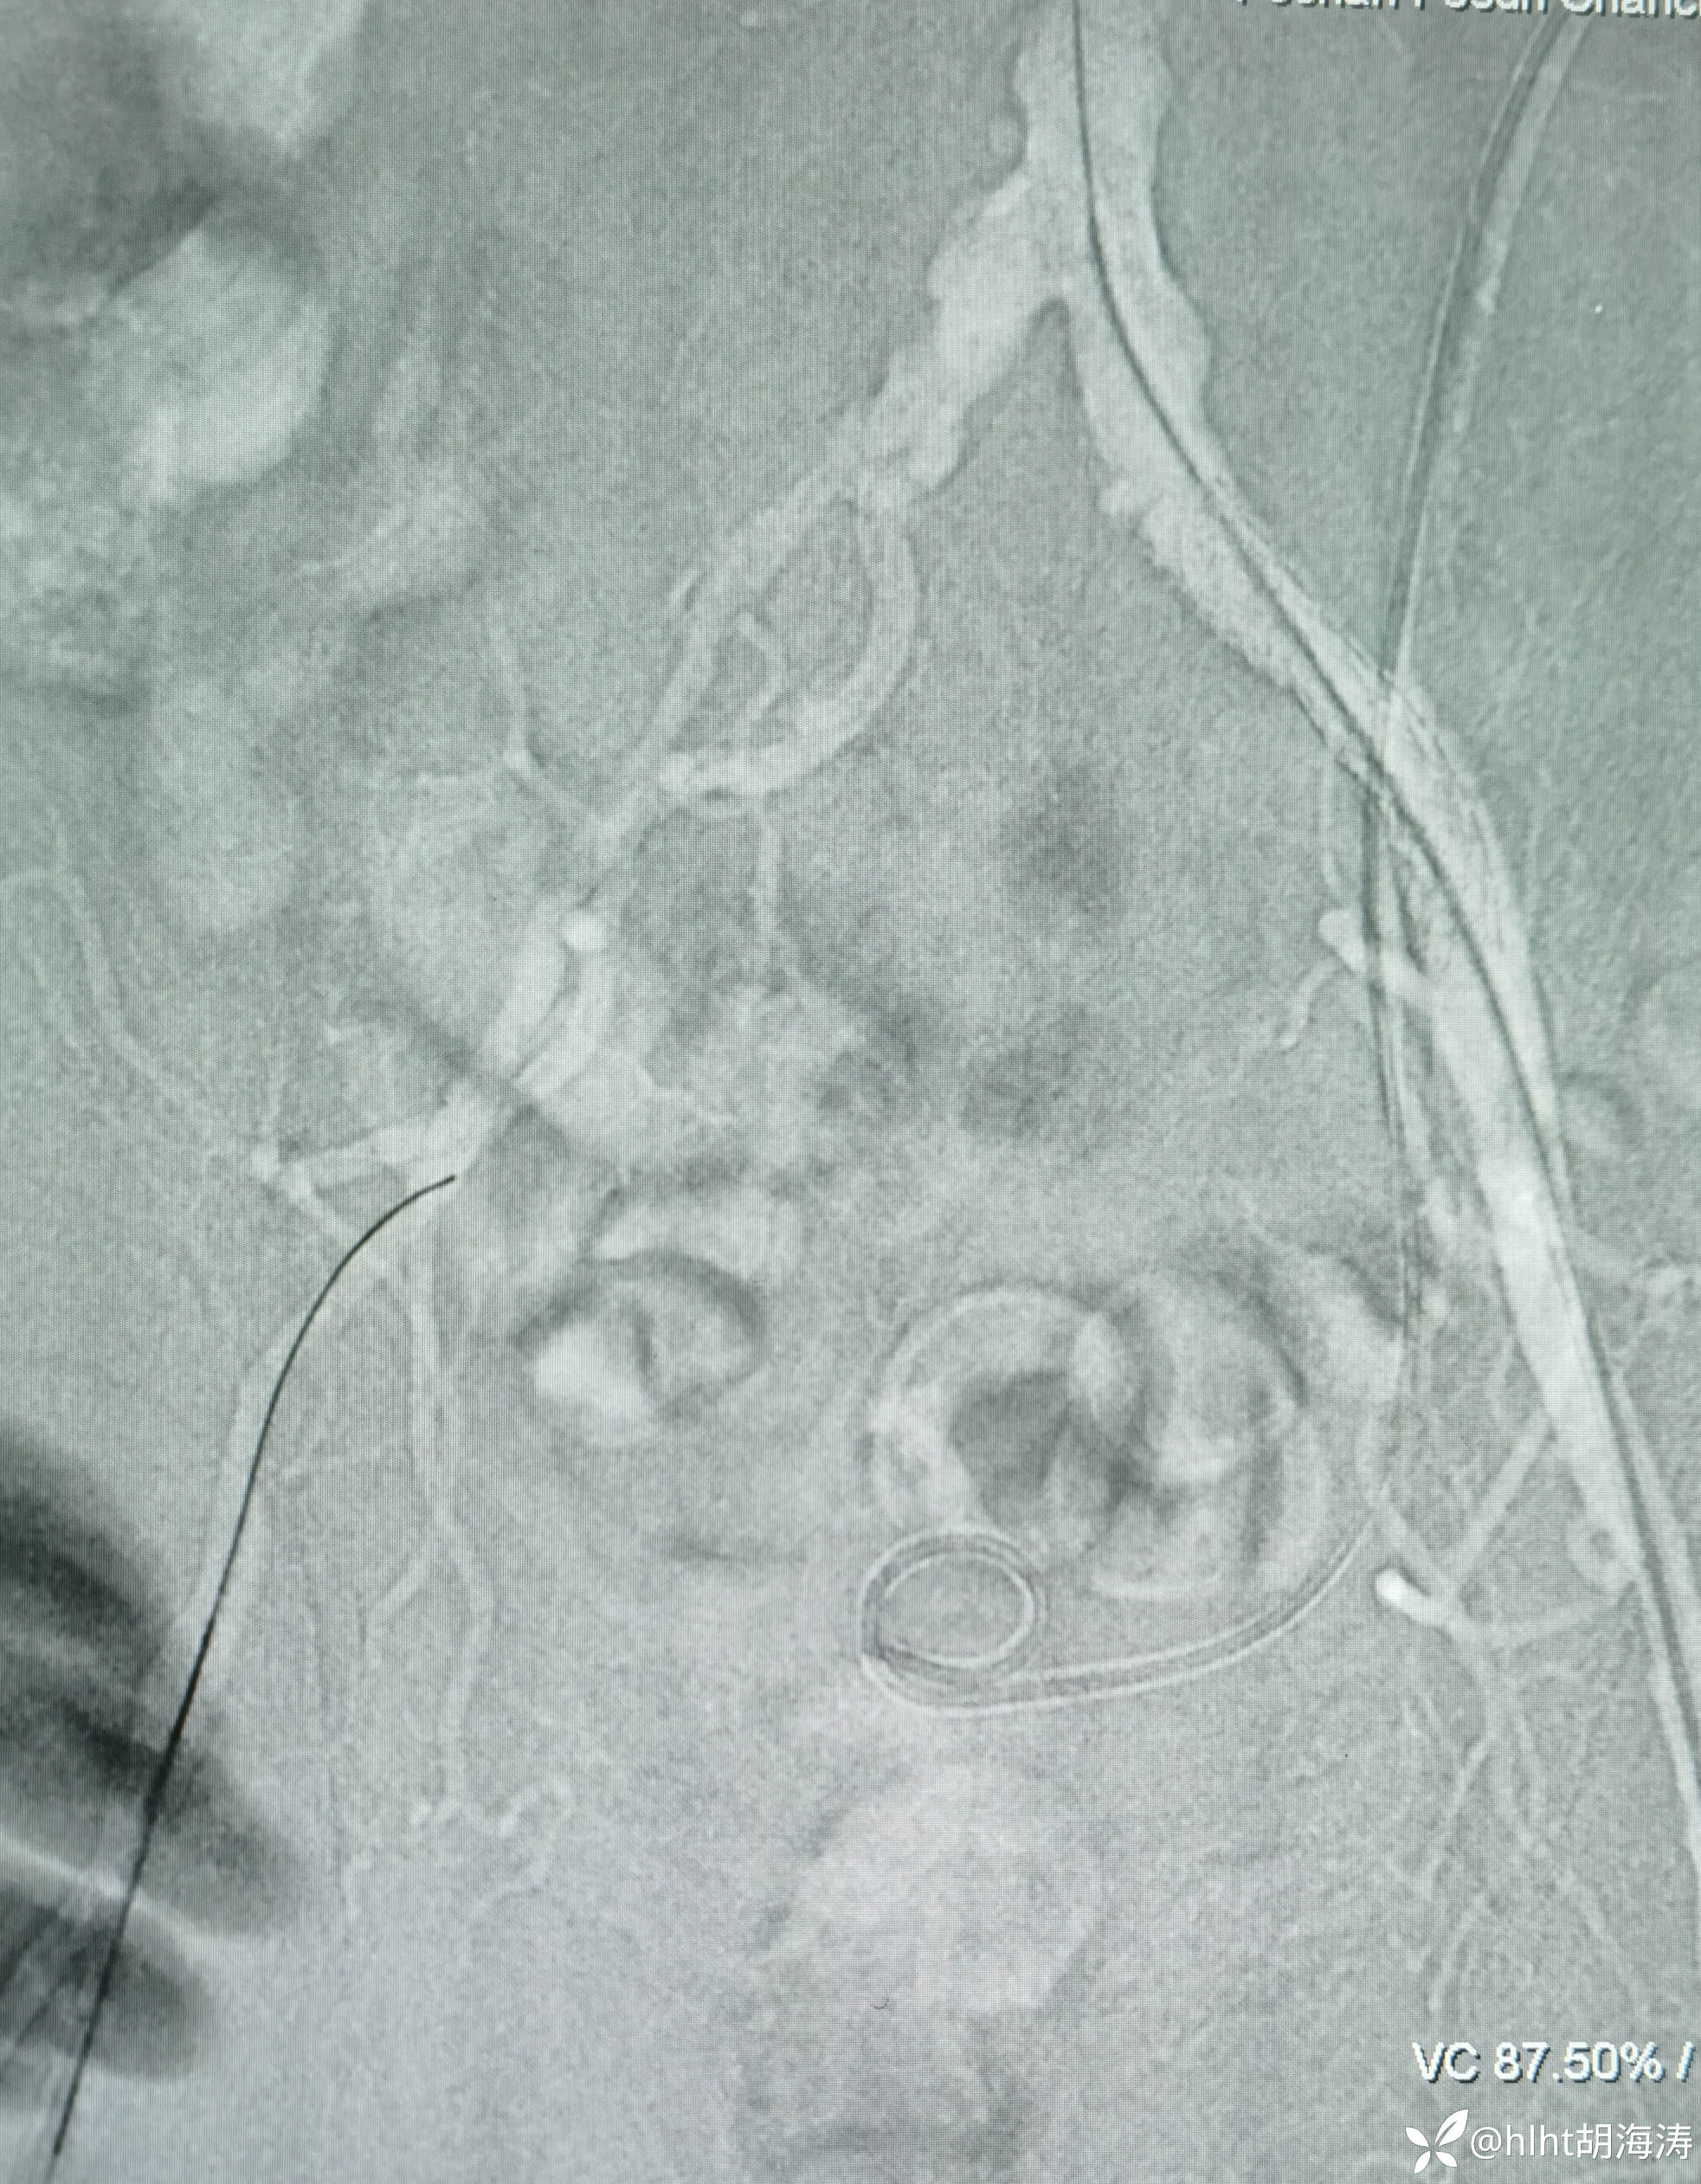

多次尝试,翻山,导丝没法进入左髂外,然后右侧腹股沟区穿刺:微创针

置入5F血管鞘:造影提示右侧髂外开口处重度狭窄

右侧髂外动脉直径不到左侧的1/2,扩到5mm,血流好,无限流夹层